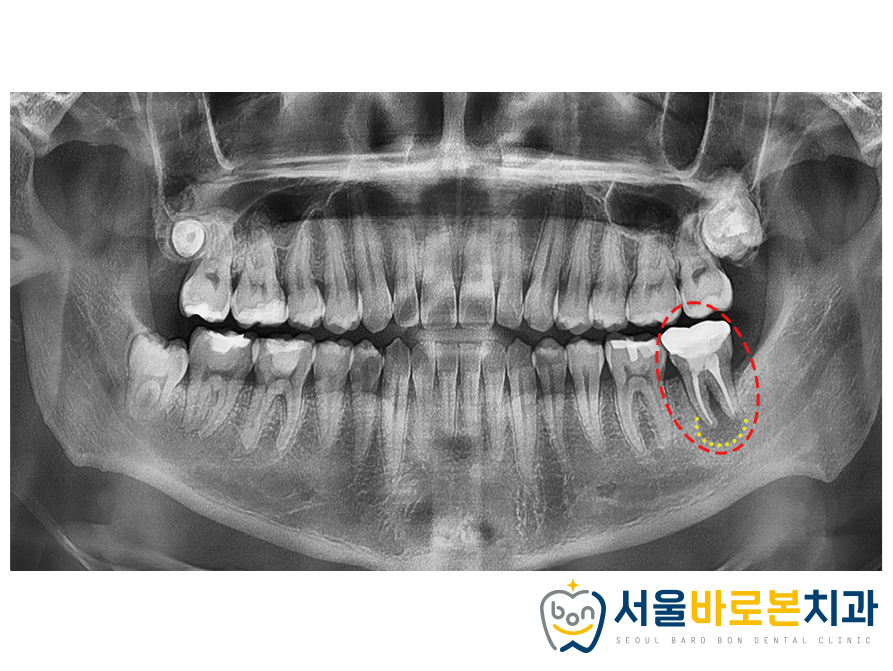

정밀한 체크를 위해

파노라마 사진을 촬영해 보았더니

불편감을 느끼고 있던 치아는

과거 신경치료 및

크라운 수복을 한 치아로

치아 뿌리 주변으로

심한 염증을 관찰할 수 있었는데요.

잇몸뼈가 녹아 뿌리 끝 주변으로

까맣게 비춰보이는 부분을 확인할 수 있으며,

잇몸뼈가 치아의 뿌리 부분만 잡고 있어

동요도까지 보이는 상황이었습니다.

심한 염증으로 인해 신경 가까이까지

치조골이 흡수된 위험한 상황이었답니다!